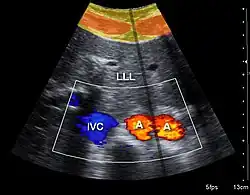

Both abdominal and endoanal ultrasound are frequently used in gastroenterology and colorectal surgery. In abdominal sonography, the major organs of the abdomen such as the pancreas, aorta, inferior vena cava, liver, gall bladder, bile ducts, kidneys, and spleen may be imaged. However, sound waves may be blocked by gas in the bowel and attenuated to differing degrees by fat, sometimes limiting diagnostic capabilities. The appendix can sometimes be seen when inflamed (e.g.: appendicitis) and ultrasound is the initial imaging choice, avoiding radiation if possible, although it frequently needs to be followed by other imaging methods such as CT. Endoanal ultrasound is used particularly in the investigation of anorectal symptoms such as fecal incontinence or obstructed defecation. It images the immediate perianal anatomy and is able to detect occult defects such as tearing of the anal sphincter.

Doppler ultrasonography is used to study blood flow and muscle motion. The different detected speeds are represented in color for ease of interpretation, for example leaky heart valves: the leak shows up as a flash of unique color. Colors may alternatively be used to represent the amplitudes of the received echoes.

Doppler ultrasonography

Doppler ultrasonography employs the Doppler effect to assess whether structures (usually blood)[58][61] are moving towards or away from the probe, and their relative velocity. By calculating the frequency shift of a particular sample volume, flow in an artery or a jet of blood flow over a heart valve, its speed and direction can be determined and visualized, as an example. Color Doppler is the measurement of velocity by color scale. Color Doppler images are generally combined with gray scale (B-mode) images to display duplex ultrasonography images.[62] Uses include: